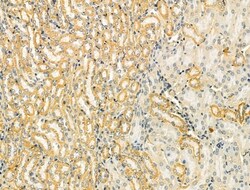

Invitrogen™ TOMM40 Polyclonal Antibody

Antibody detects endogenous levels of total TOM40.

| Immunohistochemistry (Paraffin), Western Blot | |

| A synthesized peptide derived from human TOMM40(Accession O96008), corresponding to amino acid residues R173-Q223. | |